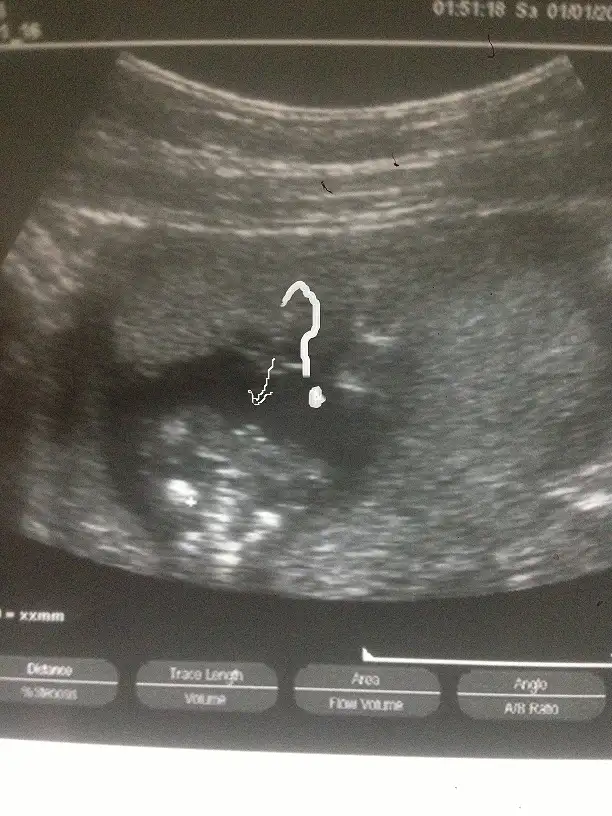

benim ufaklıgıda tahmin edebilirmisinnn 15 haftalık olduk doktor söylemiyor çıldırıcam :)))

resimleri gönderiyorum canımm bekliyorm haberlerini :)

Erkek15+2 biki doktor farklı söyledi kafam karıştı kızlar??? tahminlerinizi bekliyorum

Kızlar lütfen bir kişi yorum yaptı anlayanlardan yorum bekliyorum.11 haftalik bebeğim meraktan öleceğim lütfen acil yorum yapın anlamıyorum ben.

ORKDM ve kizlar benimkinede bi bakarmisiniz 11+4 ultrasonum var catlicam meraktan bi kizim var acaba bu bebisim ne :)

Canim ben bunuda erkege benzettim :)Kızlar bana da bişi söyleyin 10+0 iz burda..